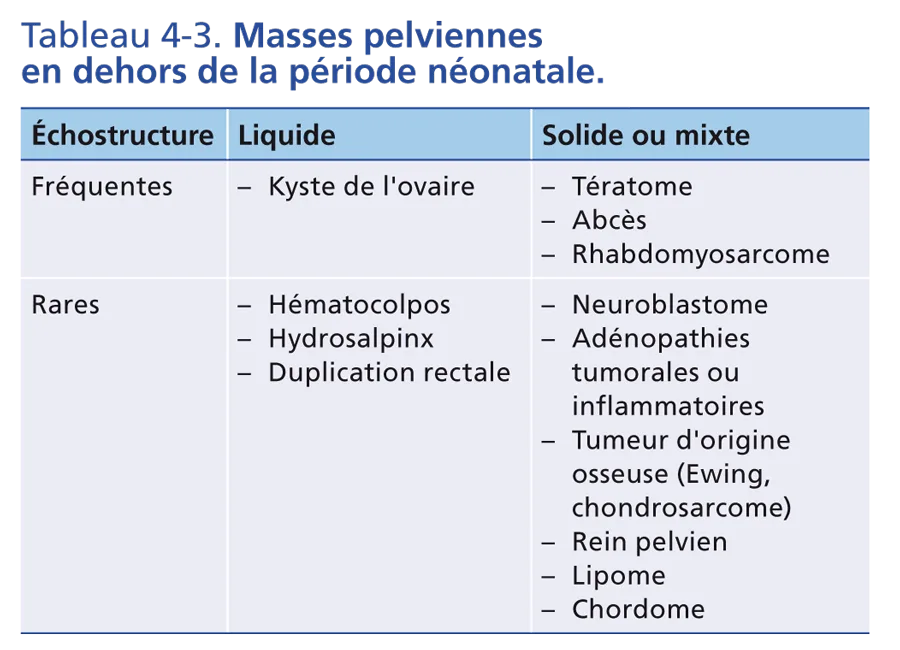

Masses pelviennes en dehors de la période néonatale

Elles sont présentées selon leur échostructure dans le tableau 4-3, trois pièges diagnostiques sont à écarter : un volumineux fécalome, un rein pelvien et une grossesse chez la jeune fille pubère.